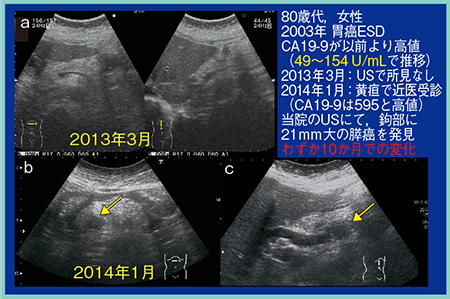

症例2は,80歳代,女性。2003年に胃癌を内視鏡的粘膜下層剥離術(ESD)にて治療している。膵癌の腫瘍マーカーであるCA19-9が以前より高値で,49〜154U/mLで推移していたため経過観察が行われていたが,2013年3月の超音波検査では膵臓に異常は認められなかった(図8 a)。2014年1月に黄疸のため近医を受診し,CA19-9も595U/mLときわめて高値であったため当院にて超音波検査を施行したところ,膵鉤部に腫瘍径21mmの膵癌とSMVなどへの浸潤が認められた(図8 b,c)。わずか10か月での急速な進行であった。

図8 症例2:腫瘍マーカー高値例の膵鉤部癌